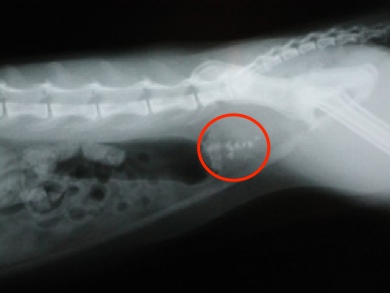

Urinary stones are solid collections of minerals that form in the urinary tract of cats, and yes, they look and feel like real stones. As you can imagine, these are extremely painful!

Urinary stones are diagnosed using x-rays or ultrasound. Since cats that have formed a urinary stone are at a high risk for recurrence, veterinarians often recommend medication or dietary changes for them to help keep urine pH regulated.